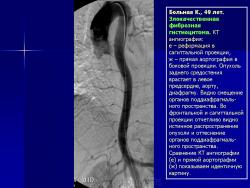

Средостение.  "Опухолевый рост".